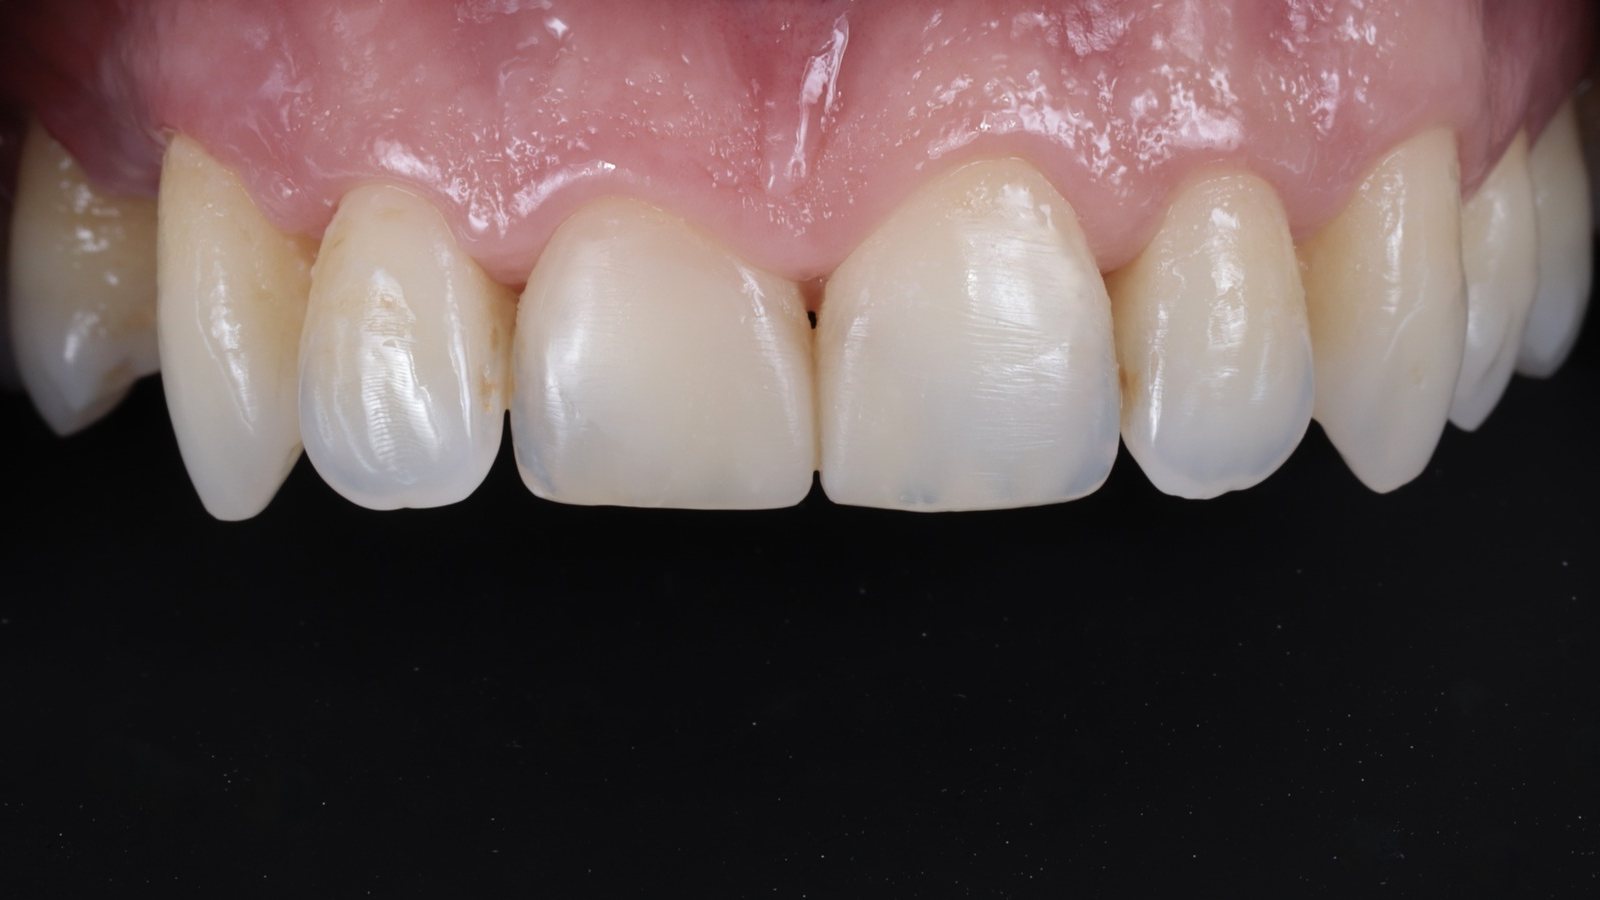

The restorations achieved complete integration with the natural tooth tissue after rehydration. The composite independently developed areas of translucency based on the thickness created, resulting in a highly aesthetic and natural appearance.

This case study demonstrates the effectiveness of Venus Pearl Pure Shades in achieving natural and aesthetically pleasing restorations, as Dr Riccardo Baratto agrees: “Venus Pearl Pure Shades are a fantastic product. It is very versatile, easy to use and simplifies many aspects of the restoration process. Its ability to set independently in relation to its contour greatly improves the shade setting process.”